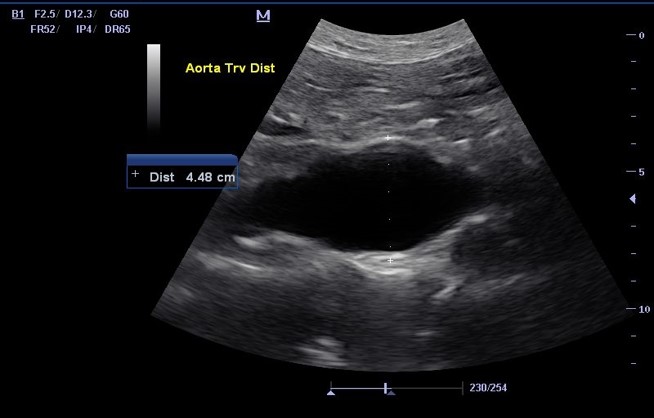

<p>What is this structure ?</p>

What is this structure ?

Abnormal Aorta

<p>What is starting to from in this Aorta?</p>

What is starting to from in this Aorta?

A blood clot